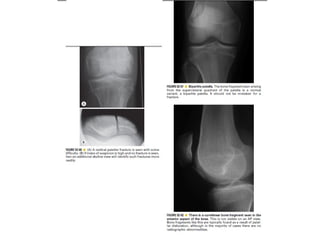

Skeletal trauma was presented by Dr Laith Fadhel with reference to Grainger's Diagnostic Radiology textbook. The presentation covered skeletal trauma as assessed through diagnostic radiology techniques. Key findings and treatments for skeletal injuries were likely discussed.